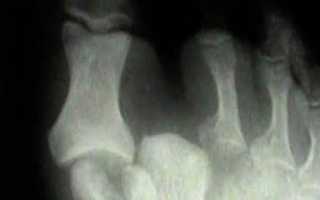

Травма диагностируется на основе визуального осмотра и рентгеновского снимка.

Диагностика Вывихов фаланг пальцев стопы:

Диагностика вывихов пальцев основывается на анамнезе, характерной деформации и положении пальцев, укорочении, ограничении функций, пружинящей неподвижности и результатах рентгенографии.

Наиболее часто встречаются вывихи дистальной фаланги I пальца, что связано с большой подвижностью этого сустава и высокой функциональной нагрузкой на I палец. Второе место занимают вывихи фаланг IV пальца. Вывихи средних пальцев встречаются реже, поскольку они лучше защищены благодаря центральному расположению. Вывихи пальцев стопы чаще происходят в тыл и в стороны, а вывихи в подошвенную сторону крайне редки из-за мощного связочно-сумочного аппарата в этой области.

Вправление вывихнутого пальца следует проводить до появления отека мягких тканей. После его развития успешное вправление становится затруднительным, особенно для вывихов средней фаланги в подошвенную сторону и вывихов в проксимальном межфаланговом суставе.